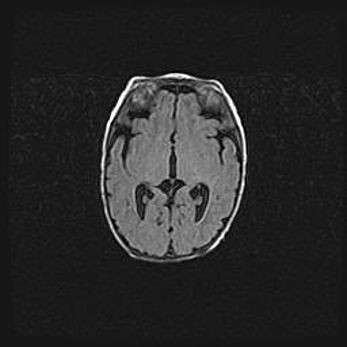

Сообщающаяся гидроцефалия. Кистозная энцефаломаляция головного мозга.

Возраст: 3 месяца 4 дня

Вес: 3100 г

Пол: женский

Окружность головы: 34 см

Срок гестации: 31 неделя

Кистозная энцефаломаляция головного мозга - одна из форм поражения головного мозга в детском возрасте. Характеризуется возникновением множественных и распространённых кист в коре, белом веществе и подкорковых образованиях головного мозга у плодов, новорождённых и детей раннего возраста. Развитие кистозной энцефаломаляции связано с внутриутробной асфиксией и гипотонией, родовой травмой, тромбозом синусов, пороками развития сосудов, инфекциями, сепсисом и другими причинами. Наиболее значимые инфекционные агенты: вирусы простого герпеса, цитомегалии, краснухи, токсоплазмы, энтеробактерии, золотистый стафилококк и другие.